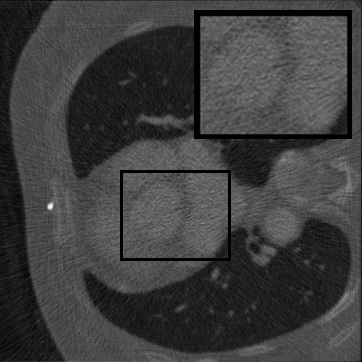

Figure 2: Qualitative inpainting results on TomoBank (lines 1 to 2) and LoDoPaB (lines 3 to 4) with random mask (ratio = 0.8) at 1024×\times1024 resolution. Odd columns and even columns show the sinograms and reconstructed images, respectively.

Inpainting Quality. Tab 2 summarizes accuracy results. At 2048×\times2048 resolution, HiSin achieves the best performance among all baselines while remaining memory-efficient, demonstrating its ability to extend high-quality inpainting to resolutions where other diffusion models fail. At 1024×\times1024, HiSin delivers accuracy comparable to its computation-intensive counterpart RePaint, showing that our optimizations do not compromise fidelity at moderate scales. Compared to DiffIR and HiDiffusion, HiSin consistently achieves higher SSIM and PSNR across mask ratios, with improvements up to +0.03 SSIM and +1.8 dB PSNR. Fig 2 visualizes sinogram inpainting and reconstructed images, where HiSin produces nearly indistinguishable results from RePaint. These findings confirm that HiSin fundamentally extends diffusion-based inpainting to 2048×\times2048 resolution in a more memory- and runtime-efficient manner.